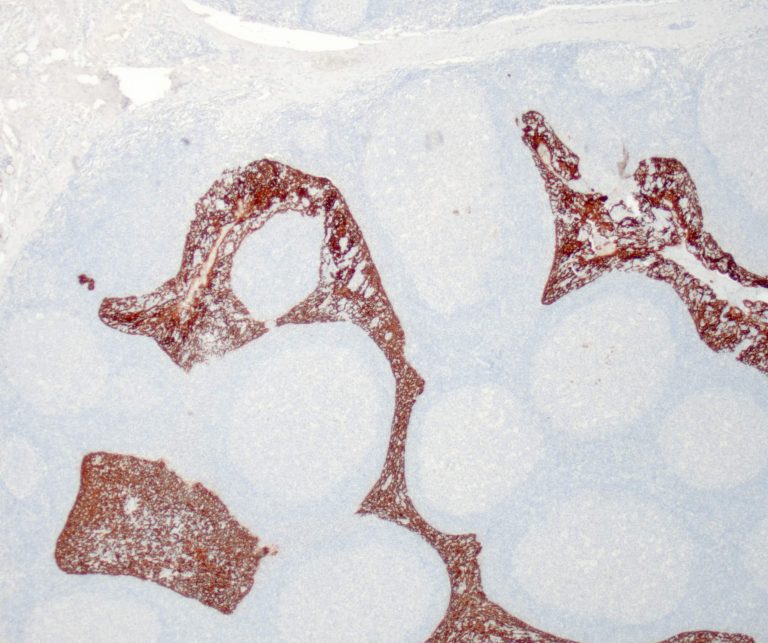

Lung Pathology